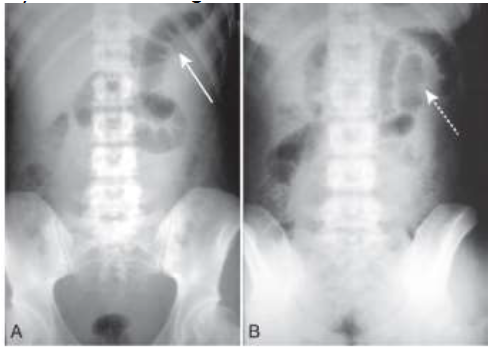

Observe as imagens abaixo:

Paciente dá entrada no pronto atendimento com quadro de dor abdominal súbita, moderada, acompanhada de vômitos de conteúdo alimentar. Diabético, em uso irregular de hipoglicemiante, com história de etilismo. Apresenta-se pálido, mucosas secas, redução do turgor da pele, auscultas cardíacas e pulmonares preservadas, abdome distendido, com ruídos hidroaéreos reduzidos e dor à palpação de todo abdome. Solicitados exames laboratoriais e exame radiológico do abdome (imagem anexa acima).

Qual é o diagnóstico radiológico?